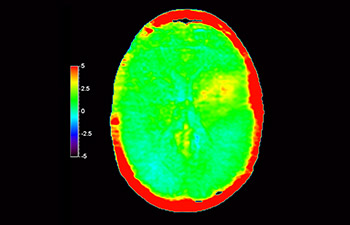

Astrocytoma 3d apt

Brain astrocytoma, post-radiotherapy

with 3D APT